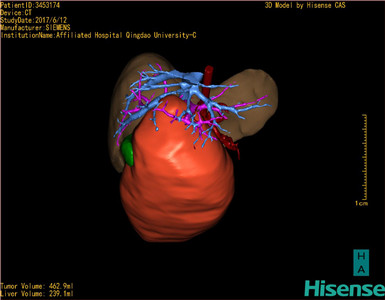

将0.625mm双源薄层CT资料的静脉期和动脉期Dicom格式文件导入海信CAS系统。

通过调节窗宽窗位调整CT序号,对肝实质,胆囊,下腔静脉,肿瘤,肝动脉、门静脉及肝静脉等进行三维重建;系统自动计算肝脏体积。

模拟手术操作,自动计算切除肿瘤体积。肝脏体积为310.9ml,肿瘤体积为437.7ml,肿瘤体积是肝体积的1.4倍,通过比对9-12月正常肝脏体积为321.13±118.91ml,通过术前模拟手术,精准判断切除后剩余肝脏体积能耐受,避免肝衰竭发生。

术前三维重建:

重建图片